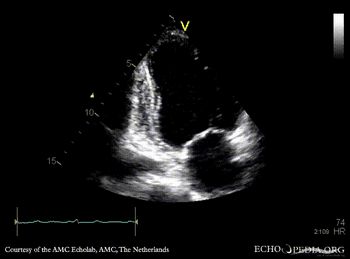

Case 95

Apical and anteroseptal infarction

A3CH